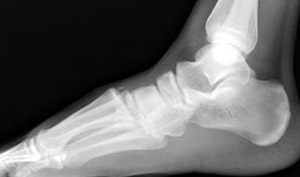

Skeletal Trauma > Foot & Heel > Foot & Heel Quiz

Metatarsal Fracture

What fracture is shown here?